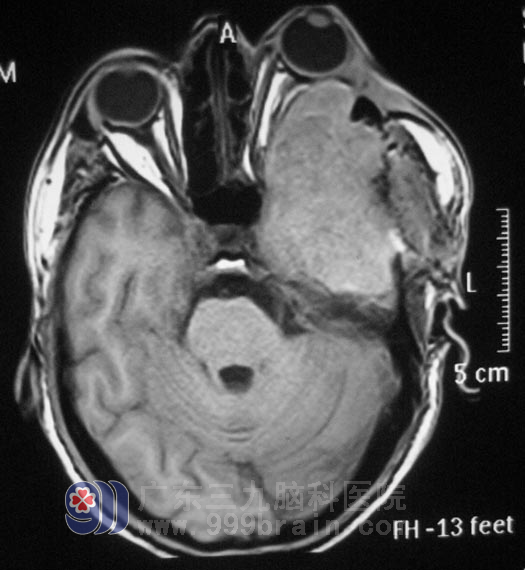

在综合神经外科,鲁明主任仔细了解病情:患者左眼外凸约2cm,充血明显,视力下降,眼球活动固定,头颅CT见病灶大小约57.7mm×85.4mm×75mm,相邻左侧颧弓、左侧额颞骨(累计左侧眼眶外侧壁、左侧上颌窦外侧壁)、蝶骨大翼左侧骨质吸收破坏,病灶向前突入眶外后,左侧眼球、左侧眼外肌受压前移并左眼明显突出,邻近左侧额颞叶脑组织受压,左侧额颞部骨质不连续。

▲手术前